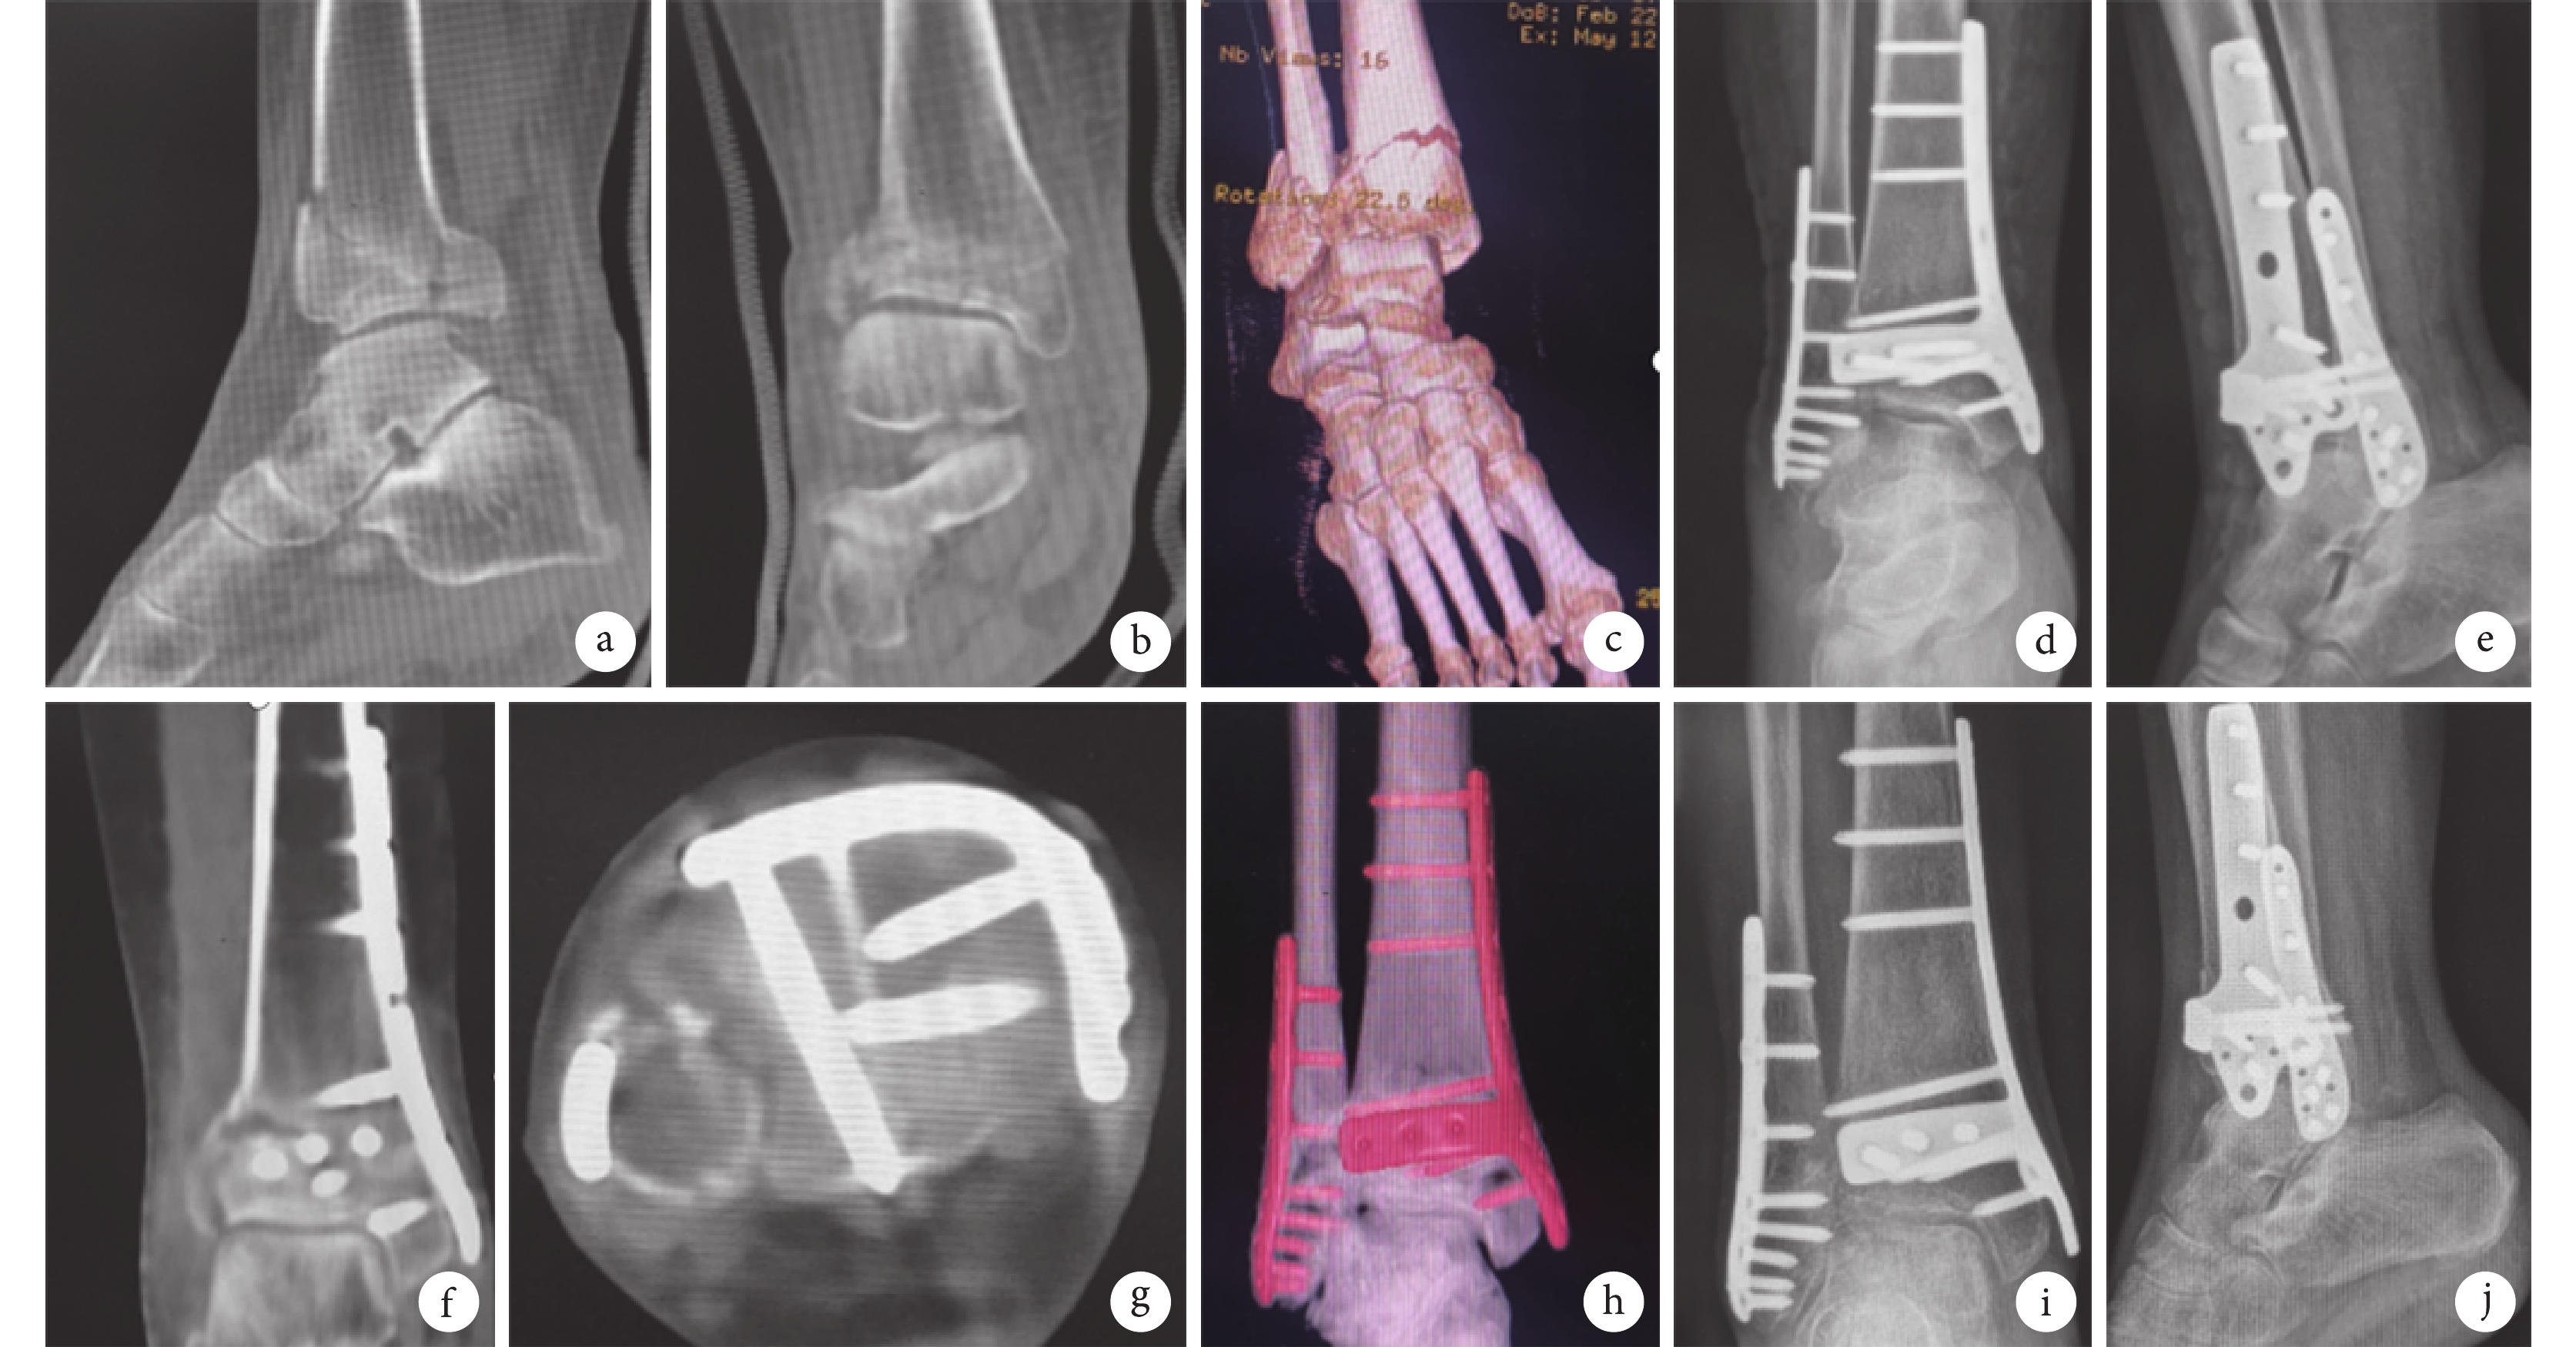

a~c. 術前CT掃描及三維重建示右脛骨遠端骨折累及關節面及干骺端;d、e. 術后3 d正側位X線片示骨折復位及內固定物位置均良好;f~h. 術后3 d CT掃描及三維重建示關節面復位良好;i、j. 術后6個月正側位X線片示骨折愈合

Figure2. A 46-year-old female patient with type 43C2 Pilon fracture of right ankle in the trial groupa-c. Preoperative CT scan and three-dimensional reconstruction showed that the fracture of the distal end of the right tibia involved the articular surface and metaphysis; d, e. Anteroposterior and lateral X-ray films at 3 days after operation showed that the fracture reduction and the position of internal fixator were good; f-h. CT scan and three-dimensional reconstruction at 3 days after operation showed that the reduction of articular surface was good; i, j. Anteroposterior and lateral X-ray films at 6 months after operation showed that the fracture healed

末次隨訪時,試驗組踝關節功能按照Johner-Wruhs評分標準[11]達優25例、良7例,優良率100%;對照組達優16例、良5例、可4例,優良率84.0%;差異無統計學意義(Z=?1.442,P=0.149)。試驗組AOFAS評分為(90.9±4.5)分,對照組為(85.2±10.0)分,差異有統計學意義(t=2.651,P=0.012)。隨訪期間除對照組1例發生踝關節創傷性關節炎外,兩組均無踝關節畸形愈合、鋼板松動、斷裂、骨折復位丟失等并發癥發生。見圖2、3。